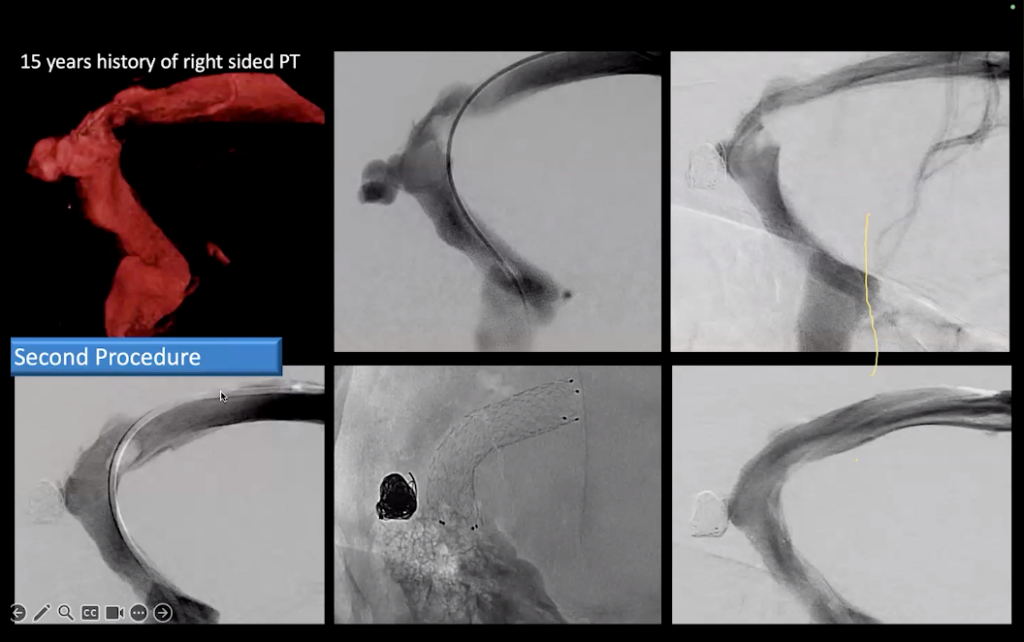

On January 14th, 2026 Dr. Mohamad K. AbdalKader presented Venous Diverticulum and its role in Pulsatile TinnitusA whooshing or throbbing noise heard in one or both ears that can range from annoying to debilitating. Highly associated with venous sinus stenosis. Click the term to read more.